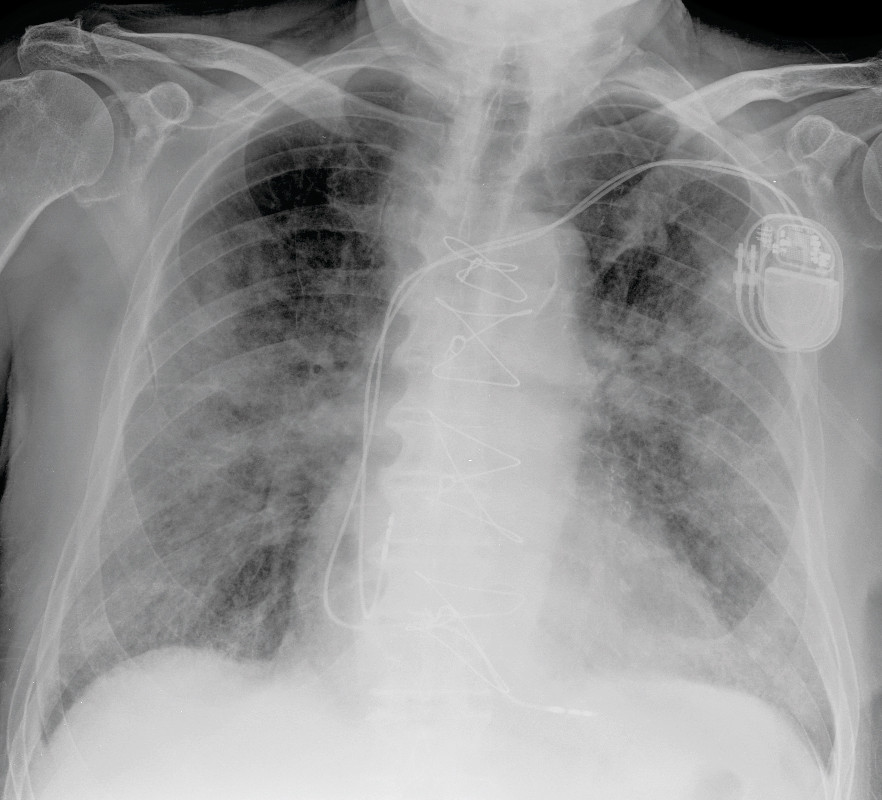

Fastlegen hadde kjent pasienten gjennom mange år. Fra tidligere hadde han hypertensjon, trekar hjertesykdom med gjennomgått nedreveggsinfarkt, kronisk obstruktiv lungesykdom i stadium 2 i henhold til GOLD-kriteriene, og benign prostatahyperplasi. Grunnet AV-blokk grad 2 type 2 med venstre grenblokk hadde han fått implantert en tokammer pacemaker ni måneder før den aktuelle hendelsen. Ekkokardiografi utført i den forbindelse viste god venstre ventrikkel-funksjon uten signifikante klaffefeil. Pasienten gikk jevnlig til kontroller hos fastlegen, og tok sine medisiner som foreskrevet. Han hadde sluttet å røyke for 40 år siden og hadde et lavt alkoholforbruk. Til tross for alvorlige kroniske lidelser var pasienten til vanlig helt selvhjulpen og oppegående og hadde ikke behov for ganghjelpemidler. Han kjørte bil og hadde gjennomført førerkortvurdering med god kognitiv skår. Han var aktiv som frivillig på flere arenaer.

Hurtigtest for influensa og RS-virus i akuttmottaket var negativ, og dråpesmitteregimet ble derfor opphevet. Røntgen thorax viste ingen lungeforandringer. Pasienten fremsto ikke septisk preget. På mistanke om lungebetennelse med bakterielt agens ble pasienten innlagt og gitt empirisk behandling med intravenøs benzylpenicillin.

Røntgen thorax viste ikke overbevisende tegn til stuvning, men økende løst mettede fortetninger med økende konsolidering som indikerte sykdomsprogresjon (figur 2). Utover kvelden på sykdomsdag 7 ble han stadig mer besværet i pusten, med respirasjonsfrekvens over 40 per minutt og oksygenmetning ned mot 60 %, til tross for høyt oksygentilskudd på maske med reservoar.

Mens det første røntgenbildet av lungene på sykdomsdag 2 var uten fortetninger, hadde pasienten mattglassfortetninger i alle lungeavsnitt på pulmonal CT-angiografi utført på sykdomsdag 5. Mattglassfortetninger kan sees ved flere tilstander og gjenkjennes ved at forandringene ikke overskygger lungestrukturene. Slike med eller uten konsolidering er beskrevet hos pasienter med covid-19 (11−14). Konsolidering er fortetninger hvor lungens normalanatomi utviskes. CT skal ikke brukes som diagnostisk verktøy eller screeningverktøy, men kan være aktuelt i tilfeller hvor det er mistanke om komplikasjoner som ikke er avklart på røntgen thorax (15). CT kan være mer sensitiv enn rRT-PCR i tidlige stadier av sykdommen og i et epidemisk område, men er ikke spesifikk, og andre interstitielle pneumonier vil kunne gi lignende funn (16)−(17). CT vil for disse pasientene være en meget begrenset ressurs, fordi det må gjøres tidkrevende smittevask av laboratoriet mellom hver undersøkelse. Det ble ikke tatt ny CT i sykdomsforløpet til vår pasient, men på sykdomsdag 7 ble det tatt røntgen thorax som viste økende løst mettede fortetninger med økende konsolidering (figur 2). Dette indikerte sykdomsprogresjon.